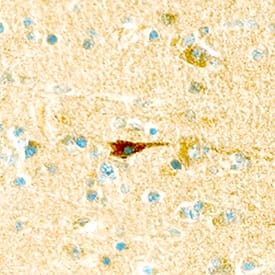

Leptin R antibody in Human Brain by Immunohistochemistry (IHC-P).

Leptin R in Human Brain.

Leptin R was detected in immersion fixed paraffin-embedded sections of human brain using Goat Anti-Human Leptin R Antigen Affinity-purified Polyclonal Antibody (Catalog # AF389) at 25 µg/mL overnight at 4 °C. Tissue was stained using the Anti-Goat HRP-DAB Cell & Tissue Staining Kit (brown; Catalog # CTS008) and counterstained with hematoxylin (blue). Specific staining was localized to neurons. View our protocol for Chromogenic IHC Staining of Paraffin-embedded Tissue Sections.